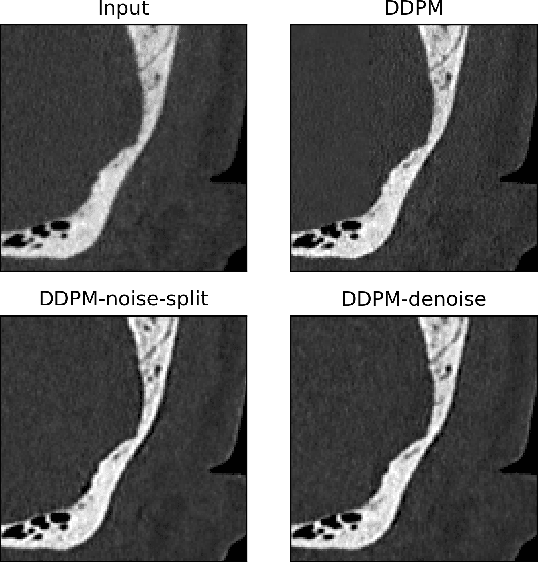

Abstract:Ultra-high resolution images are desirable in photon counting CT (PCCT), but resolution is physically limited by interactions such as charge sharing. Deep learning is a possible method for super-resolution (SR), but sourcing paired training data that adequately models the target task is difficult. Additionally, SR algorithms can distort noise texture, which is an important in many clinical diagnostic scenarios. Here, we train conditional denoising diffusion probabilistic models (DDPMs) for PCCT super-resolution, with the objective to retain textural characteristics of local noise. PCCT simulation methods are used to synthesize realistic resolution degradation. To preserve noise texture, we explore decoupling the noise and signal image inputs and outputs via deep denoisers, explicitly mapping to each during the SR process. Our experimental results indicate that our DDPM trained on simulated data can improve sharpness in real PCCT images. Additionally, the disentanglement of noise from the original image allows our model more faithfully preserve noise texture.